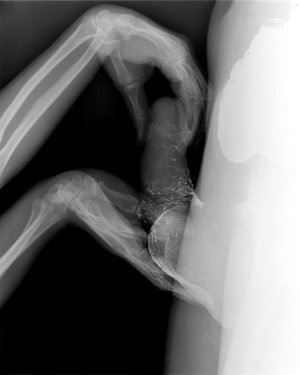

половой акт в разрезе, УЗИ, секс на рентгене

sex x-ray video

секс на томографе MRI

секс изнутри, половой акт в разрезе

как это снимал доктор Pek van Andel